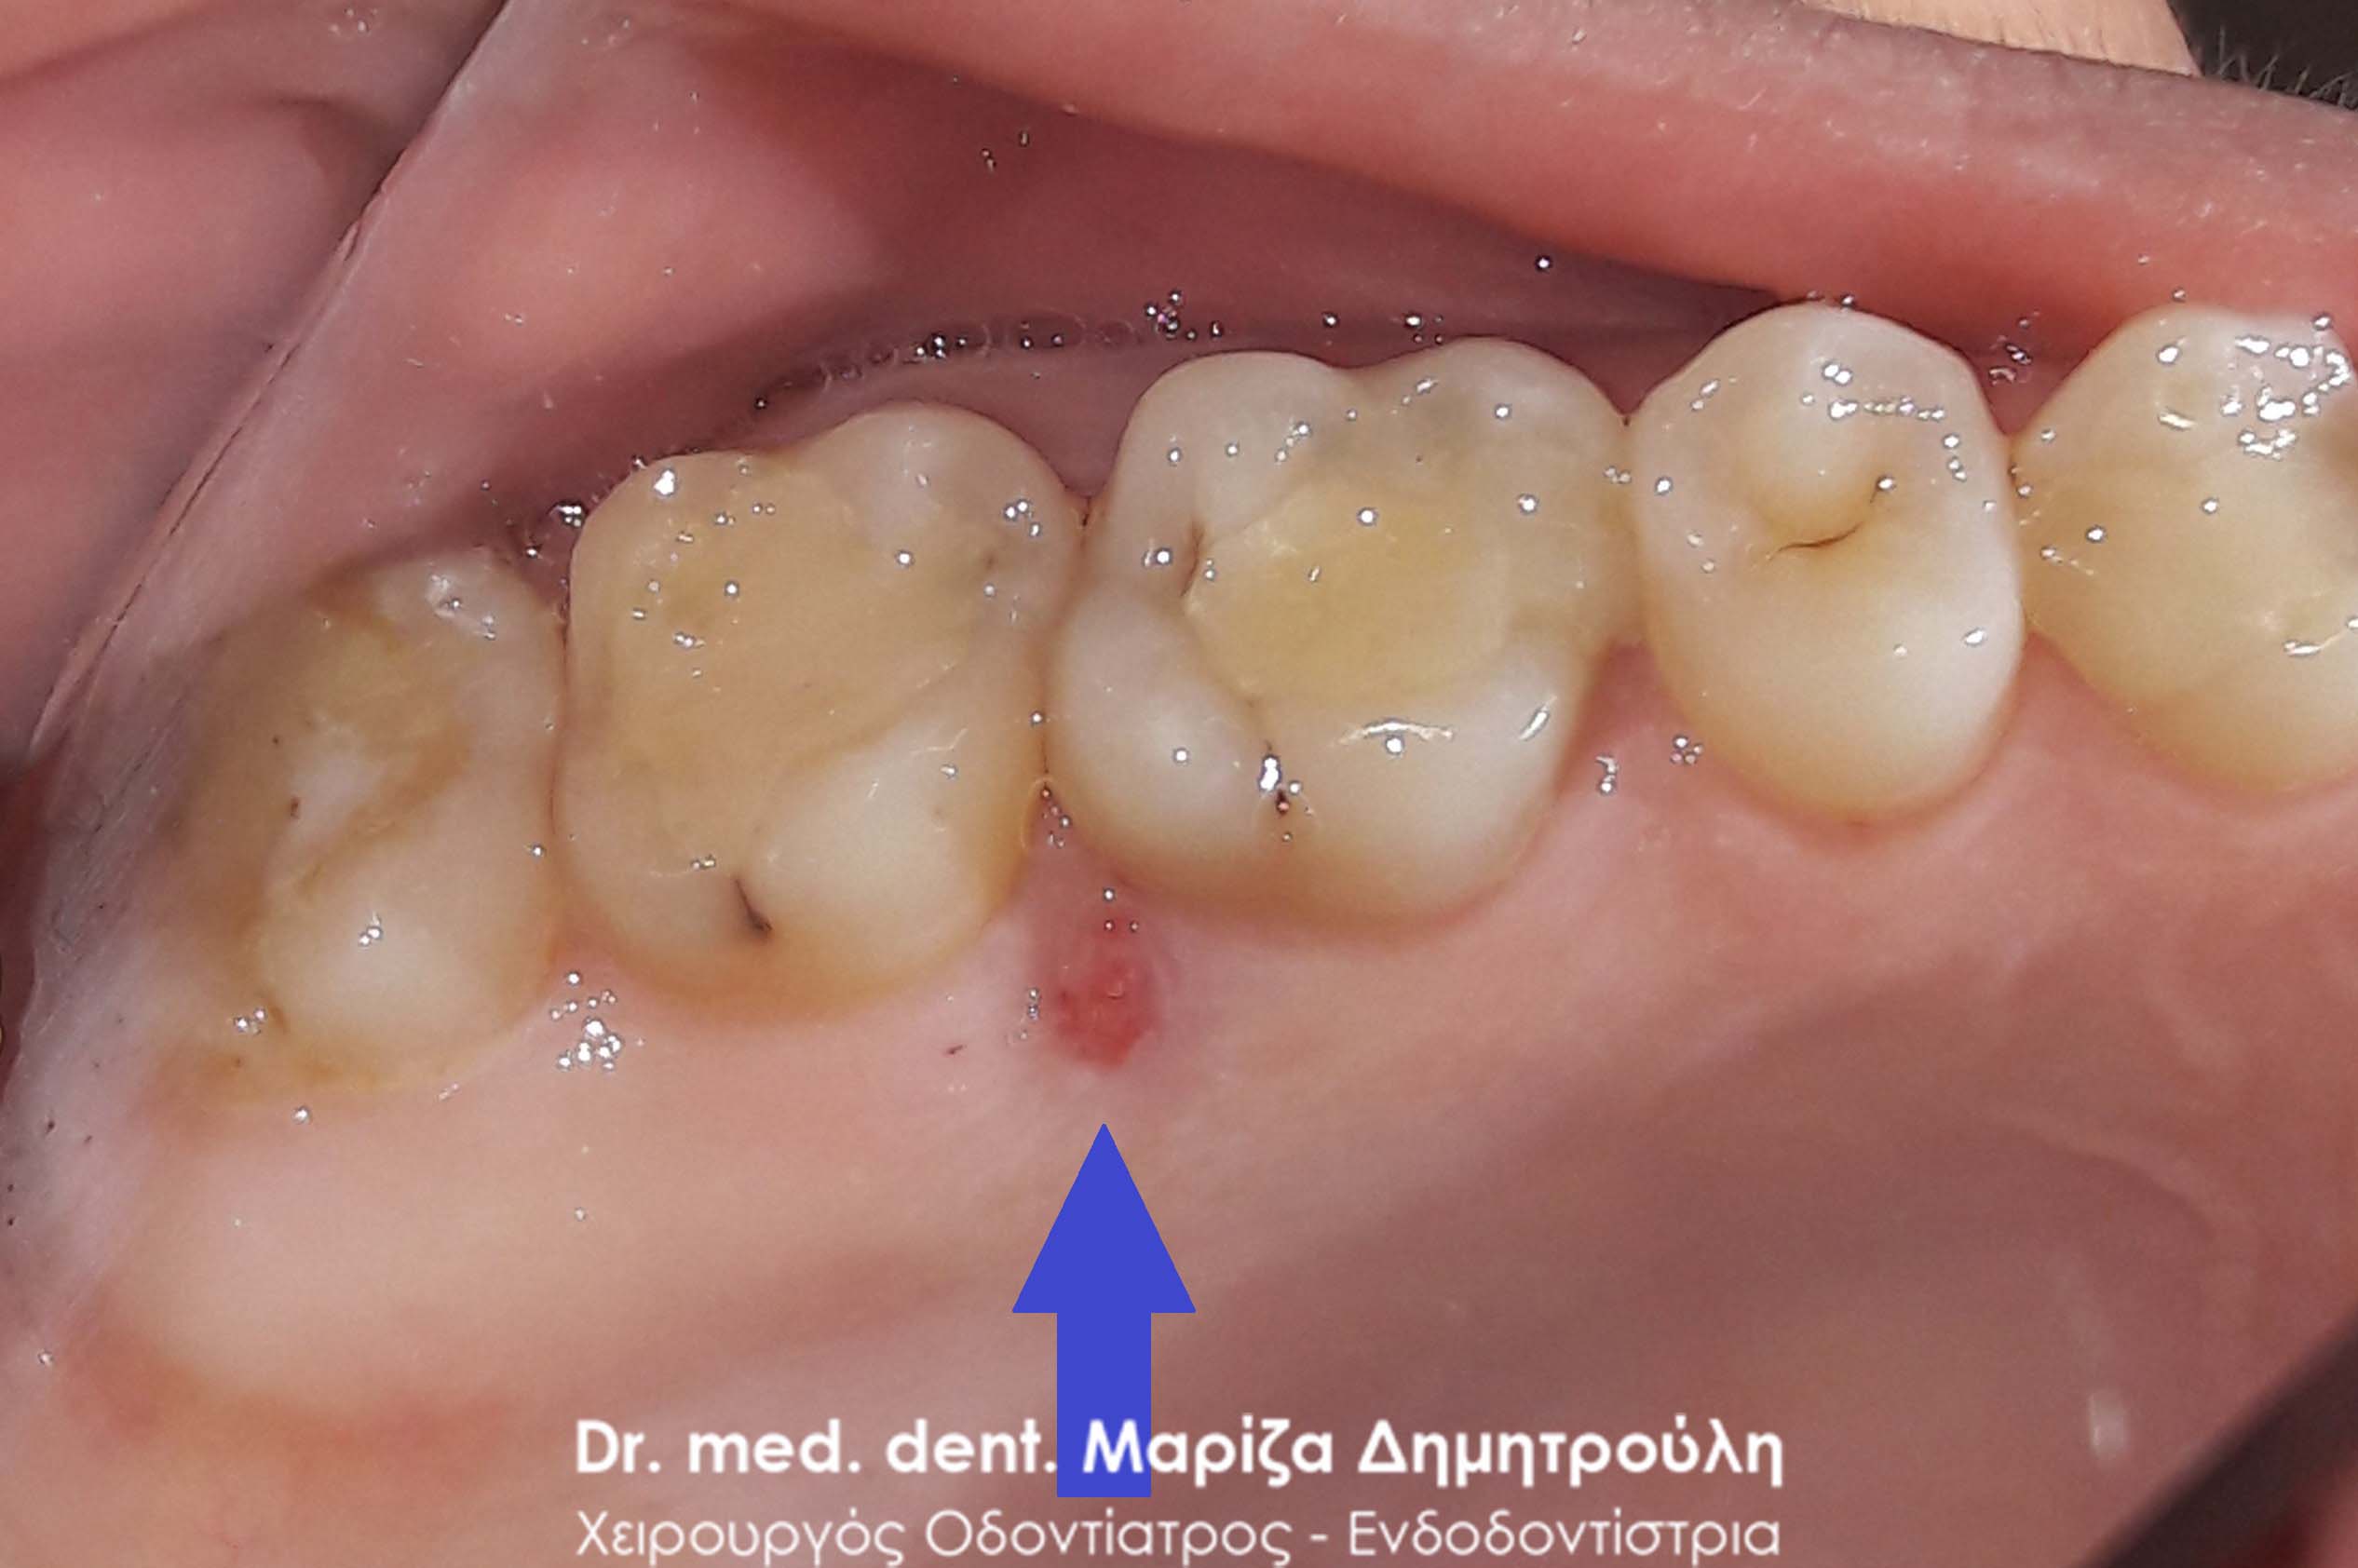

AFTER

Restoration of the tooth with white dental filling